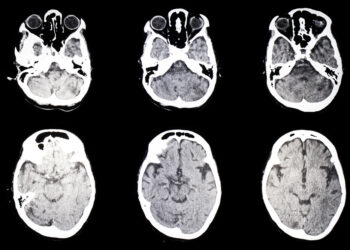

Skaityti daugiauDetailsMetachromatinė leukodistrofija (MLD) yra reta paveldima liga, kurios metu pažeidžiama centrinės (smegenų ir nugaros smegenų) bei periferinės nervų sistemos baltoji...

Skaityti daugiauDetailsMetabolinė encefalopatija – tai būklė, kai dėl tam tikrų organizmo sutrikimų neveikia smegenys taip, kaip turėtų. Dažniausiai šie sutrikimai susiję...

Skaityti daugiauDetailsMeningoencefalitas yra reta ir labai pavojinga sveikatai būklė, kai vienu metu išsivysto ir meningitas, ir encefalitas. Medicinos specialistai kartais vartoja...

Skaityti daugiauDetailsMeningokokcemija – itin reta ir pavojinga liga, kurią sukelia meningokoko bakterija, patekus į kraują. Negydoma ji itin greitai blogina būklę...